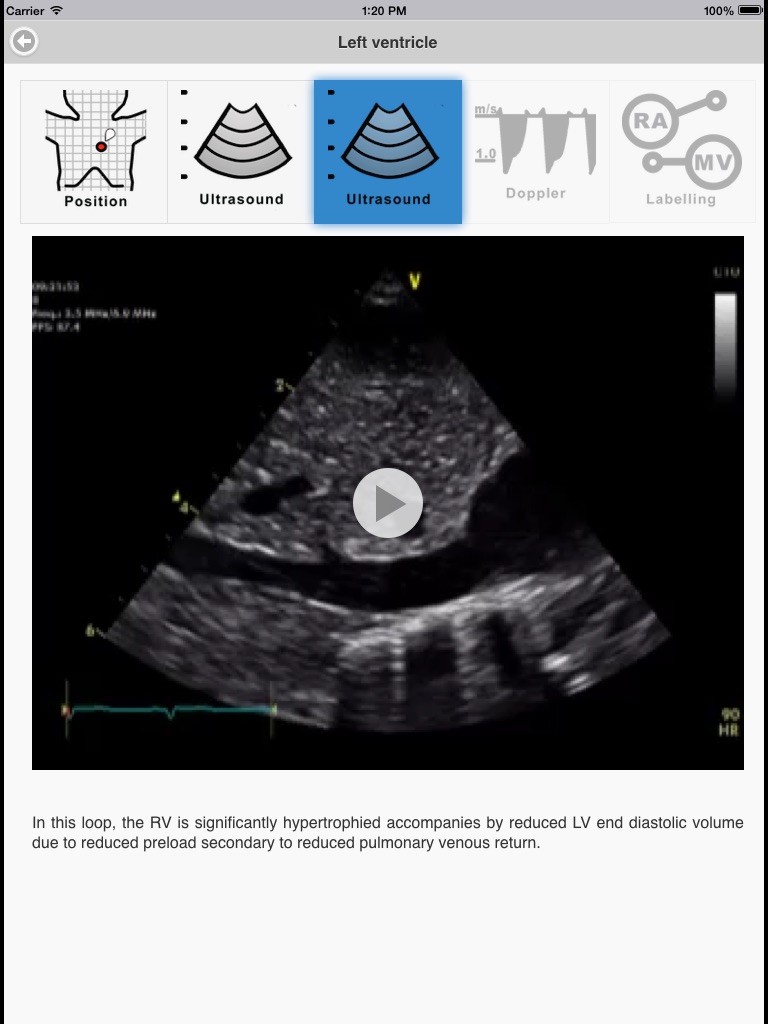

Targeted Neonatal Echocardiography (TnECHO) is increasingly used by neonatologists in the intensive care setting to support clinical decisions. The technology may be applied for the evaluation of the neonatal heart, brain, abdomen/pelvis and vascular access. This application focuses on neonatologist-performed TnECHO. The provision of real-time information on cardiovascular performance and systemic perfusion, the non-invasive nature of the technique, rapidity of data acquisition and report generation, and ability to perform longitudinal functional assessments have all contributed to in the increased utilization of TnECHO by neonatologists in the neonatal intensive care (NICU). The purpose of this application is to support neonatologists who are actively involved in a recognized TnECHO training program. This application includes videos of probe position, 2D echo loops, color Doppler loops, and labelling of the various structures. This application is aimed at familiarizing neonatologists with basic echocardiography views and aiding self directed learning, but does not represent complete training. This application has not been designed to teach how to screen, diagnose or evaluate congenital heart disease, although it is recognized that neonatologists must be familiar with normal anatomy and deviations from this. Although structural heart disease should always be considered when performing a TnECHO evaluation, if the former is clinically suspected a paediatric cardiologist should always be involved. Image optimization techniques are not discussed as it is usually machine specific.